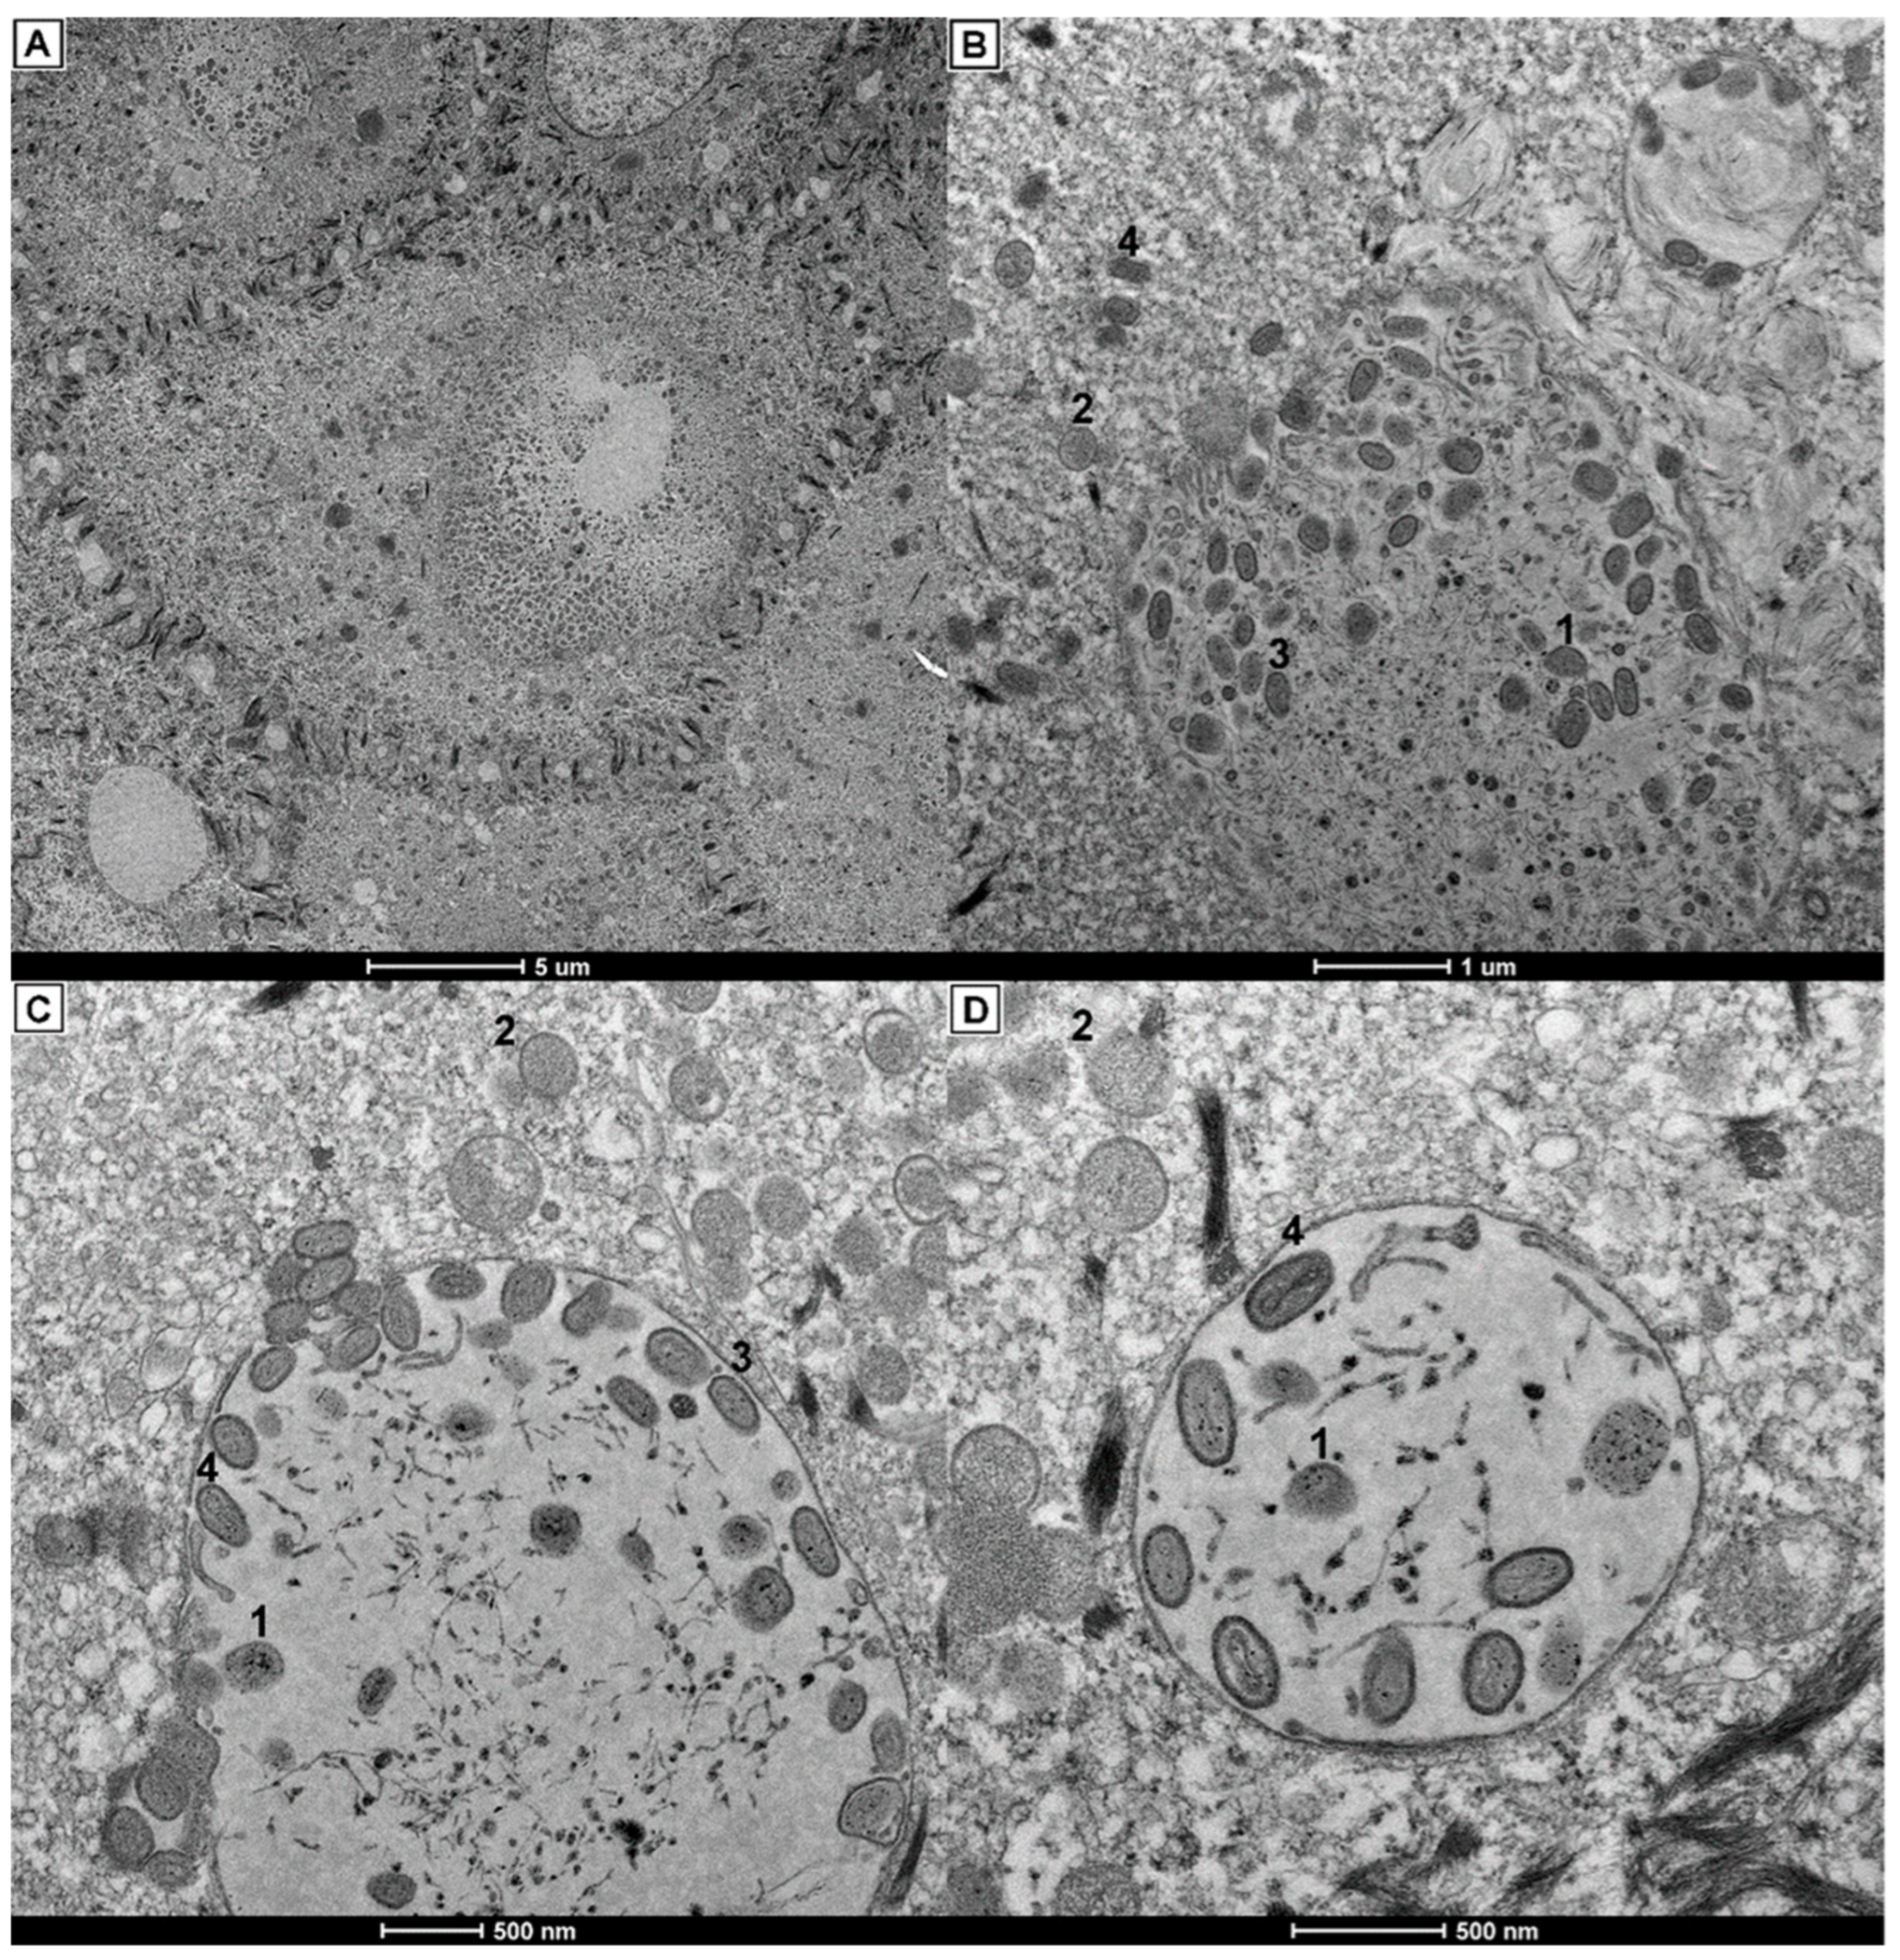

3.3. Histopathology and Electron Microscopy Findings